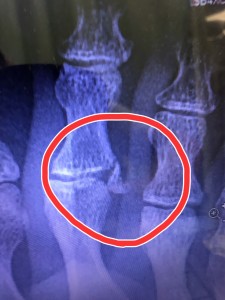

嫁と息子が相撲を取り、嫁が勝ったのですがその際足の上に息子が乗ってしまい、右第2趾を骨折してしまいました😭